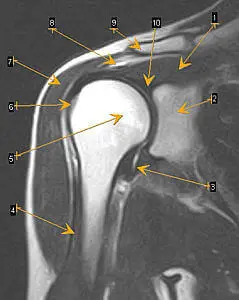

В отличии от рентгенографии на МРТ плечевых суставов кроме костных структур визуализируются мягкотканые составляющие сустава, включая хрящи, сухожилия, мышцы, связки, синовиальные сумки (рис. 1), дифференцируются дегенеративные изменения в суставе, травматические повреждения, воспалительные процессы и новообразования.

Рисунок 1.

МРТ плечевого сустава Т2 режим (коронарная плоскость)

1 – надостная мышца;

2 – суставной отросток лопатки;

3 – нижний карман полости сустава;

4 – сухожилие длинной головки бицепса плеча;

5 – головка плечевой кости;

6 – большой бугорок плечевой кости;

7 – дельтавидная мышца;

8 – поддельтовидная сумка;

9 – ключица;

10 – суставная губа.